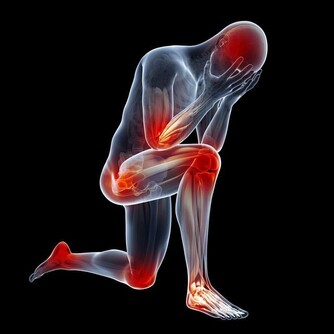

久坐:坐位可使血液循環變慢,尤其是會陰部的血液循環變慢,直接導致會陰及前列腺部慢性充血淤血。會陰部、前列腺的充血,可使局部的代謝產物堆積,前列腺腺管阻塞,腺液排泄不暢,導致慢性前列腺炎的發生。

騎車:騎車與久坐的道理一樣,可造成會陰及前列腺局部的充血,血液循環障礙,長此以往則造成前列腺炎的發生。如騎車較久會直接壓迫會陰前列腺部,可出現會陰部麻木不適,會陰疼痛,排尿時尿道痛,排尿困難,腰部酸痛等症狀,這也是我國男性慢性前列腺炎高發的主要因素之一。

對於男性的前列腺來說,最怕遇到的就是前列腺充血的情況,因為這往往會誘發前列腺炎或是前列腺癌。